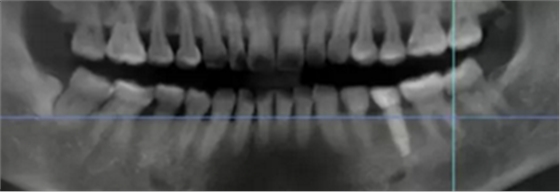

病例概述:48岁女性患者,口内健康状况良好,#35缺失多年,牙槽嵴顶骨宽度较窄。

#35缺失多年,导致#34向#35倾斜。

临牙间距不足,因此,对种植体的位置要求极高。

术前术后CBCT数据对比分析,植体就位准确。